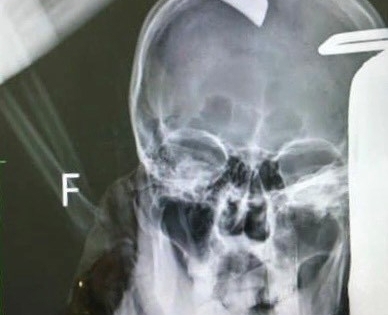

Quảng Ninh: Bênh người yêu của bạn, nam thanh niên nhập viện cùng con dao vẫn găm trên đầu

Thấy bạn gái suốt ngày bị người yêu bắt nạt, nạn nhân liền nhắc nhở bạn trai thì dẫn đến đôi bên xô xát và bị con dao bổ vào đầu.